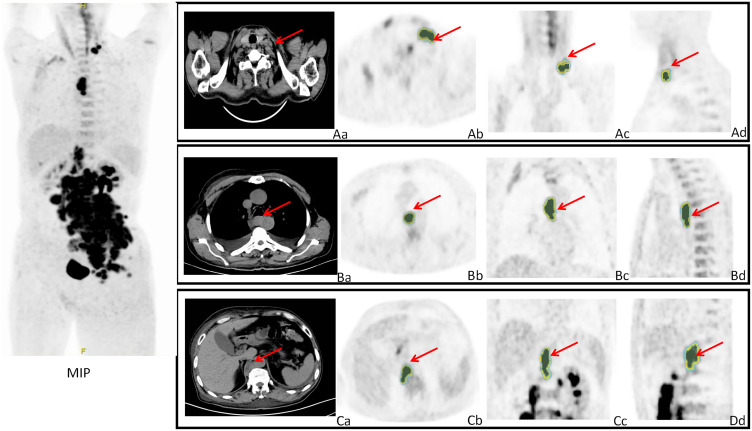

淋巴瘤是一种包括90多种亚型的造血恶性肿瘤。传统上,它们被分为两大类,非霍奇金淋巴瘤(NHL)和霍奇金淋巴瘤(HL)。基于形态学和免疫组化,HL可分为结节性淋巴细胞主导型霍奇金淋巴瘤(NLPHL)和经典型霍奇金淋巴瘤(cHL)。NHL是最常见的淋巴瘤,包括50多种亚型,如套细胞淋巴瘤(MCL)、滤泡性淋巴瘤(FL)、边缘带淋巴瘤(MZL)和最常见的弥漫性大b细胞淋巴瘤(DLBCL)。医学成像在淋巴瘤治疗中起着关键作用,正电子发射断层扫描/计算机断层扫描(PET/CT)是不可或缺的工具。2-脱氧-2-[氟-18]氟- d -葡萄糖(18F-FDG) PET/CT广泛应用于淋巴瘤治疗,已证明其在提供精确的疾病负担量化、治疗反应评估和预后评估的关键数据方面的价值。放射组学是一种创新的方法,它需要计算机辅助提取定量的、可搜索的医学图像数据及其与生物学和临床结果的关联。放射组学研究的迅速发展为癌症的诊断和治疗开辟了新的途径。我们的研究结果表明,基于人工智能的PET/CT放射组学在淋巴瘤诊断、分型、分期、治疗选择和生存预后评估方面显示出巨大的潜力,为临床医生提供了强大的决策支持工具。然而,挑战仍然存在,例如在机器学习应用中缺乏标准化的图像质量。

Lymphomas are a hematopoietic malignancies that encompass over 90 subtypes. Traditionally, they have been categorized into two main groups, non-Hodgkin lymphoma (NHL) and Hodgkin lymphoma (HL). Based on morphology and immunohistochemistry, HL can be classified into nodular lymphocyte-predominant Hodgkin lymphoma (NLPHL) and classical HL (cHL). NHL represents the most common form of lymphoma, including more than 50 subtypes, such as mantle cell lymphoma (MCL), follicular lymphoma (FL), marginal zone lymphoma (MZL), and the most common, diffuse large B-cell lymphoma (DLBCL). Medical imaging plays a pivotal role in lymphoma management, with positron emission tomography/computed tomography (PET/CT) serving as an indispensable tool. 2-Deoxy-2-[fluorine-18]fluoro-D-glucose (18F-FDG) PET/CT is extensively utilized in lymphoma management, having demonstrated its value in providing crucial data for precise disease burden quantification, treatment response evaluation, and prognostic assessment. Radiomics is an innovative approach that entails the computer-aided extraction of quantitative, searchable data from medical images and its association with biological and clinical outcomes. The rapid advancement of radiomics research has opened new avenues for cancer diagnosis and therapy. Our findings indicate that artificial intelligence based PET/CT radiomics has demonstrated significant potential in lymphoma diagnosis, subtyping, staging, treatment selection, and survival prognosis assessment, offering clinicians powerful decision-support tools. However, challenges remain, such as the lack of standardized image quality in machine learning applications.